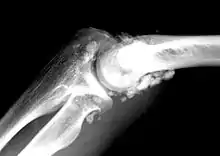

| X-ray of an elbow affected by synovial chondromatosis | |

In the early stages of the disease it is often confused with tendinosis and/or arthritis. Once it reaches transitional the loose bodies become apparent with X-ray in greater than 70% of cases, with MRI often showing where xray fails. In experienced hands, ultrasound is also useful for the diagnosis.[2]